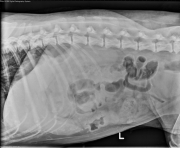

Today’s case is an adult female spayed Bouvier des Flandres with acute onset of vomiting, anorexia, and lethargy. What organ system is abnormal?

• Abdomen: The stomach is moderately distended with fluid and gas. The small intestine is distended and plicated. There is granular material in the ventral abdomen within a distended loop. There is a thin-walled round structure in the bladder on one lateral projection. There is poor detail in the peritoneal space.

• Linear foreign body in the stomach and duodenum (removed via laparotomy)